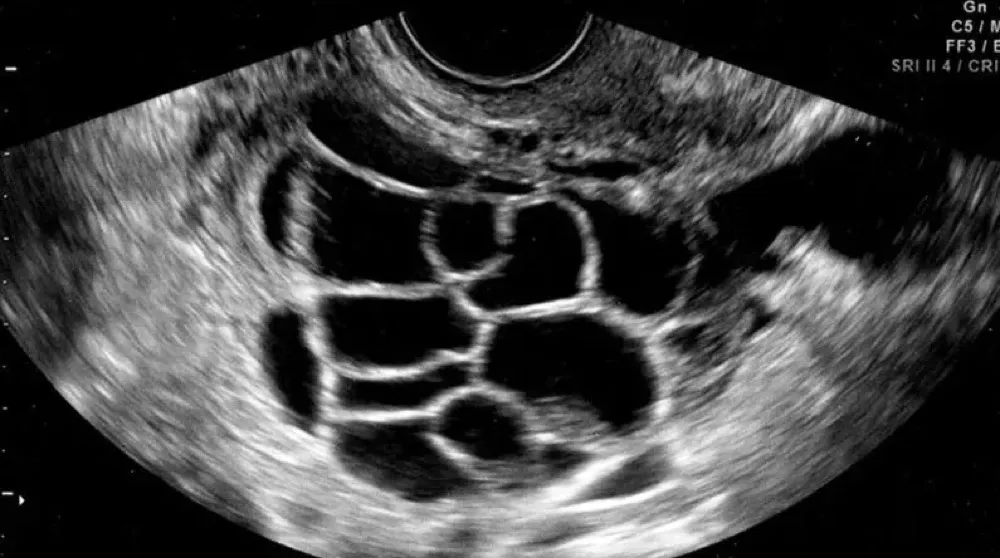

Síndrome de Hiperestimulação Ovariana causando IRAOlha esse caso clínico fora do dia a dia do nefrologista, mas que temos que estar atentos para saber conduzir de forma adequada

Valkercyo Feitosa